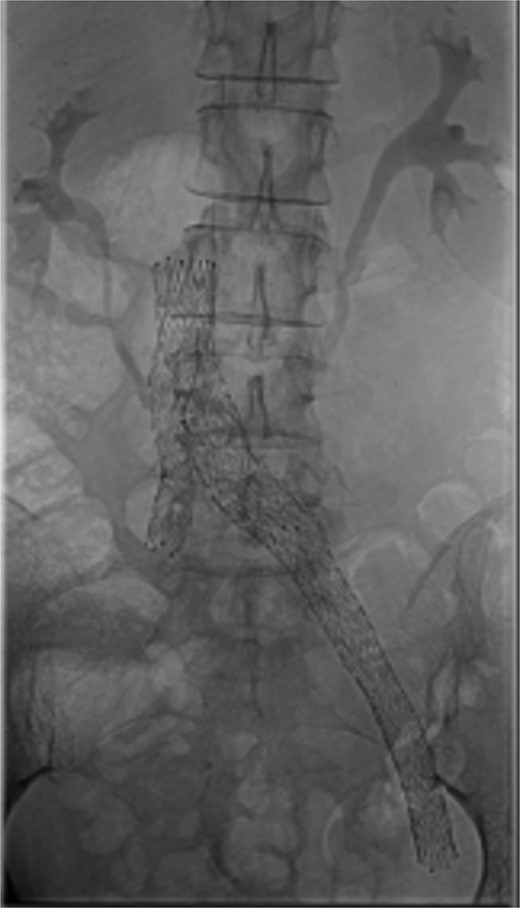

Bilateral popliteal venous access was obtained. Venography confirmed patency of the IVC, left iliac vein, and stents. Thrombolysis of the right lower limb was performed with AngioJet Zelante and 10 mg of alteplase (lower dose to minimize hematoma complications). The IVC filter was then removed to allow extension of a Venovo 12 × 80 mm stent positioned in the right iliac vein, and a Venovo 14 × 80 mm superior extension on the left. Both stents were deployed simultaneously in a ‘kissing’ configuration and post-dilatated with Mustang 12 × 100 mm balloons (Fig. 4). The completion venogram showed smooth contrast flow in both limbs with the disappearance of collateral veins.